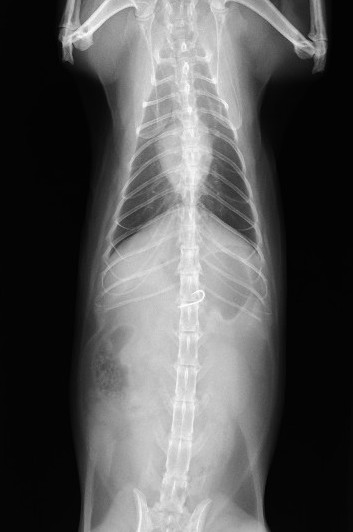

レントゲンにて胃内にX線不透過物(釣り針)、腹部エコーにてアコーディオン状に手繰り寄せられた消化管と紐状異物を確認

釣り針の誤食ならびに糸による紐状異物と診断

内視鏡検査にて胃内の釣り針を確認